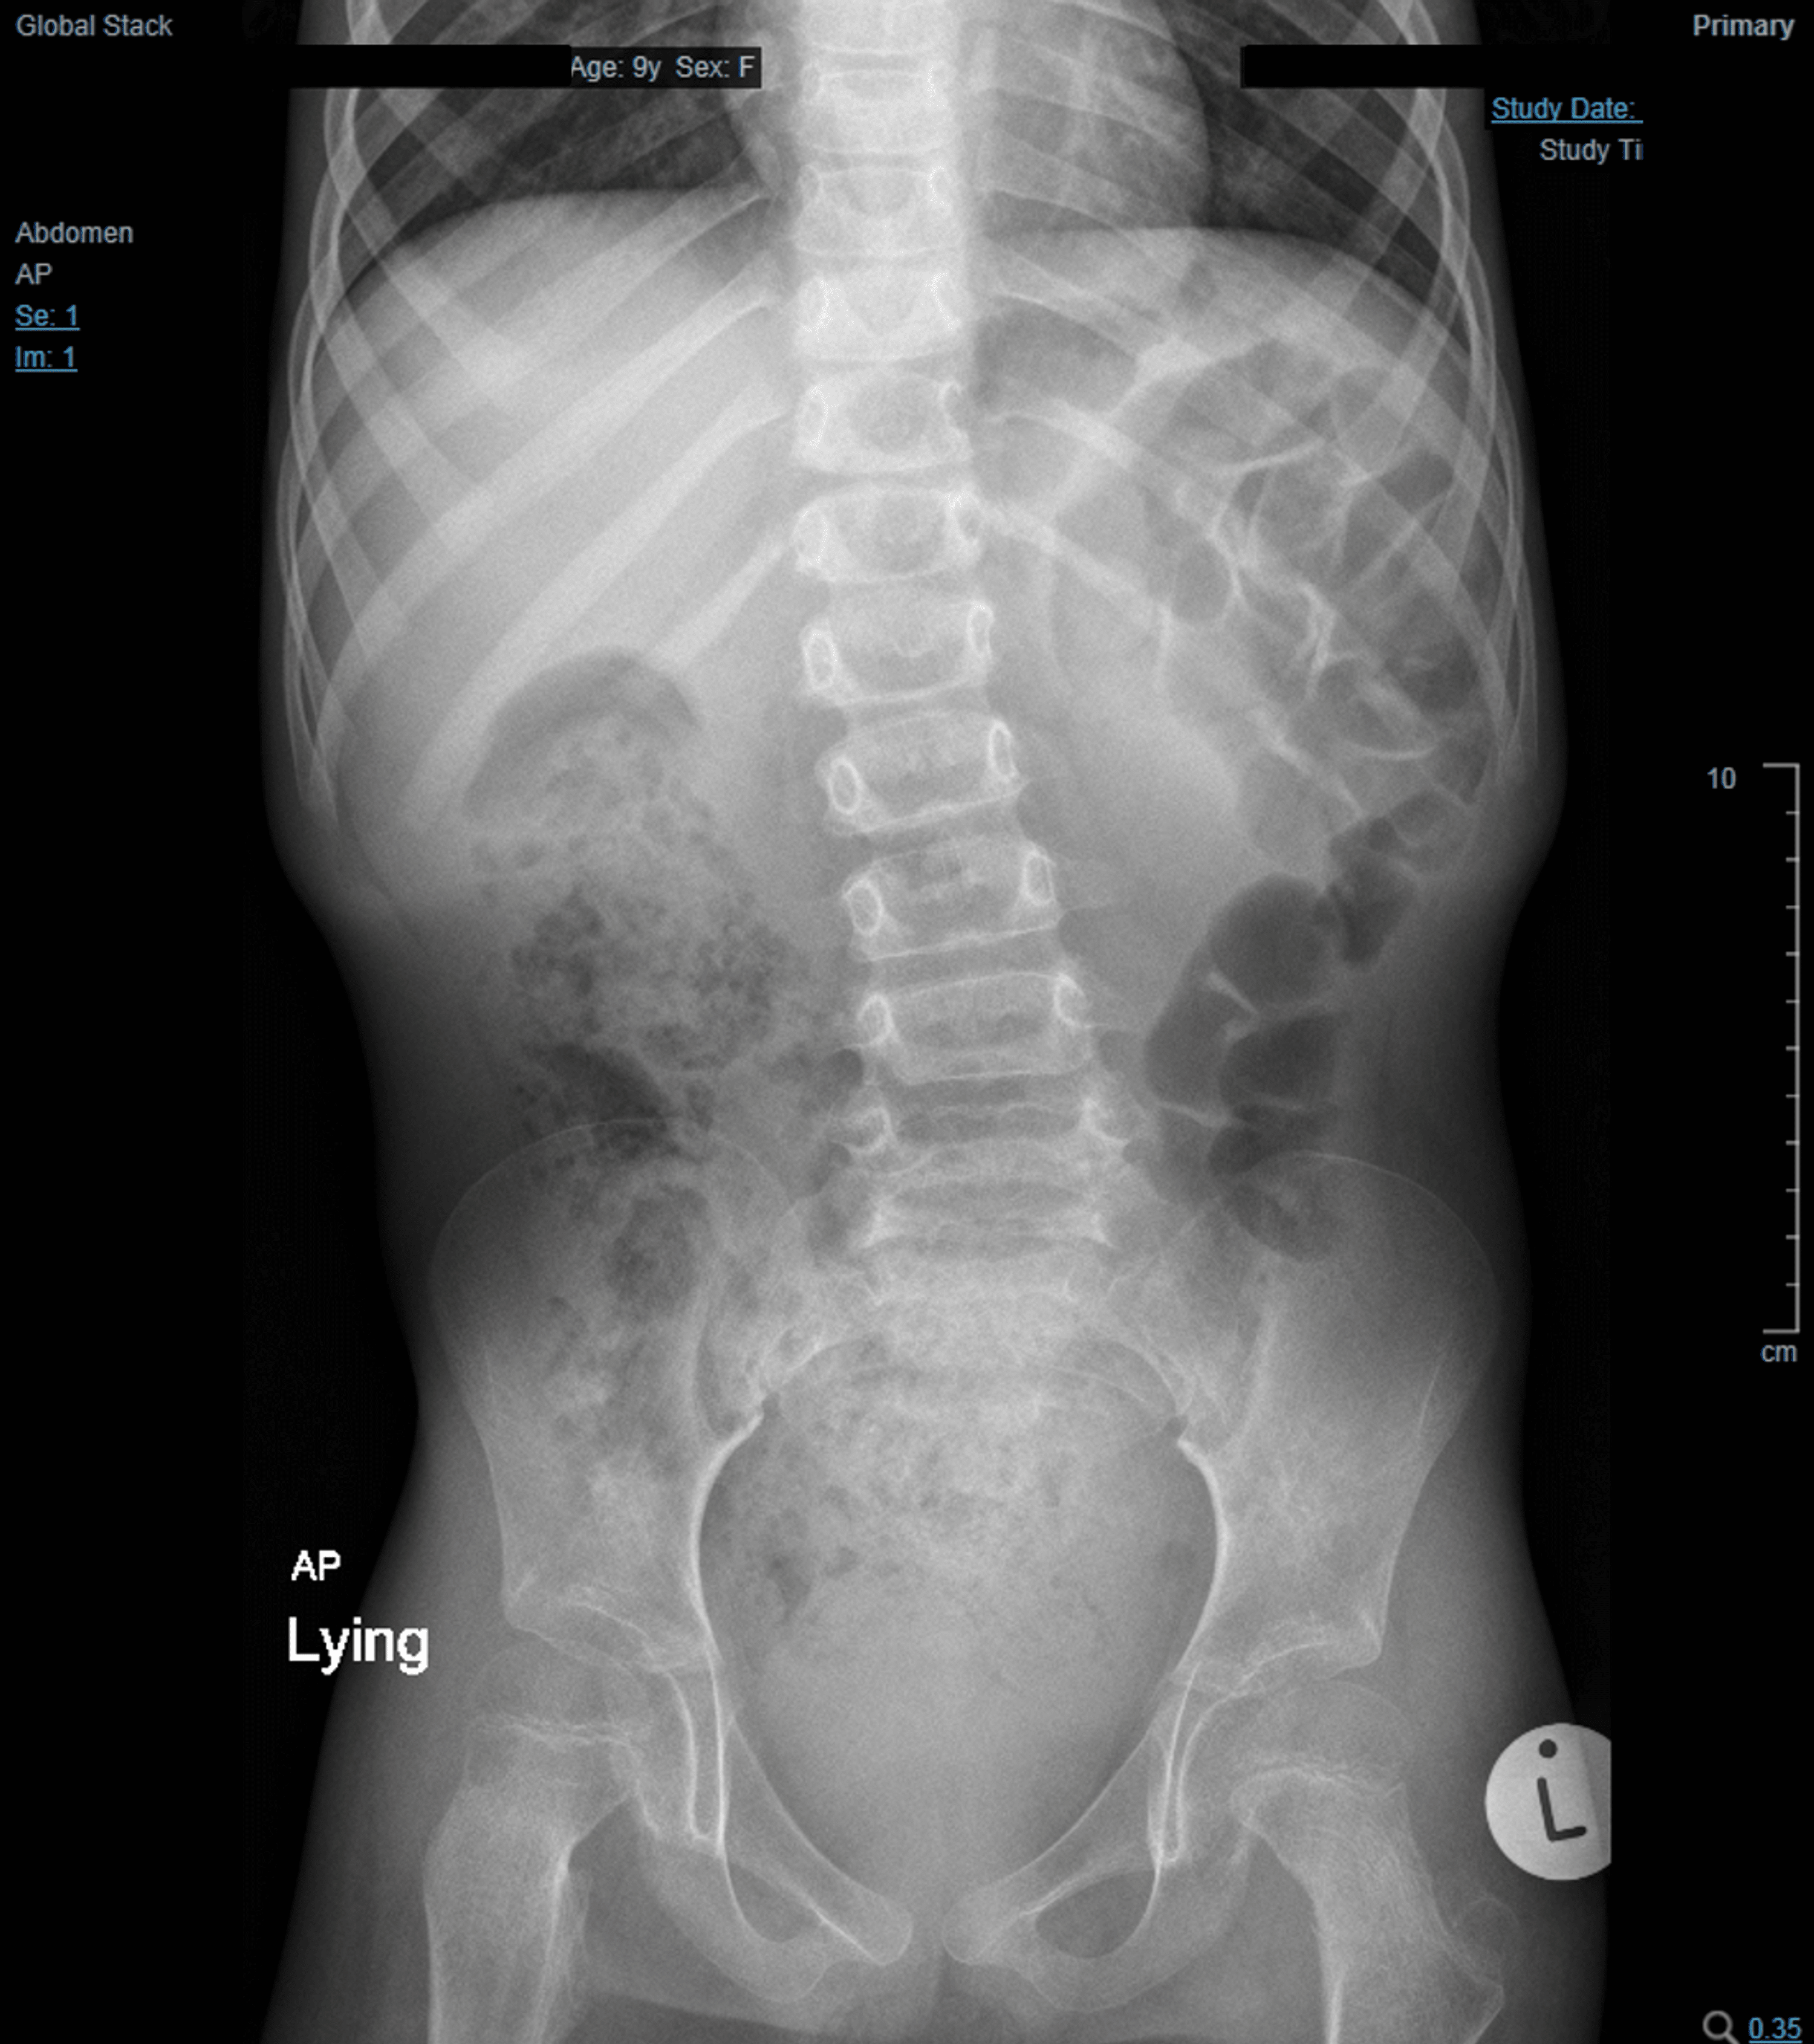

Intestinal Obstruction in a Child X Ray, Film Xray Body of Child Stock Image Image of ascites Colon Blockage In Child We'll discuss the most common symptoms & when you should talk with a doctor. Bowel & digestive problems in children can come from a wide variety of conditions. Intestinal obstruction is a blockage that keeps food or liquid from passing through your small intestine or large intestine (colon). If a section of your bowel becomes blocked, you'll need to be. Colon Blockage In Child.